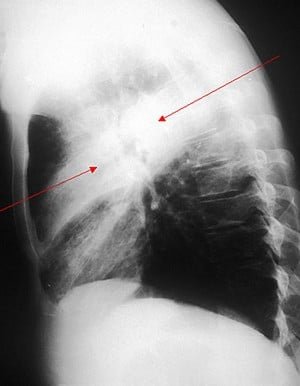

Розповідь про інфільтративні зміни часто починається з рентген-знімка – лікар дивиться на зображення ваших легенів і бачить щось, що там бути не повинно. Так, там з’явилися ділянки з підвищеною щільністю. Чому? Можливо, це запалення, рідина, фіброз… або щось гірше? Отже, коротка відповідь – це зміни в тканинах легенів, які викликані наявністю сторонніх часток чи тканинних компонентів, які туди просто-напросто не повинні потрапляти.

- Рентген грудної клітини: на цей етап сподівання завжди великі, але він може лише вказати на підозру.

- Комп’ютерна томографія (КТ): ось це вже цікавіше. Дає детальніші зображення, дозволяючи розпізнати різні патерни інфільтрації.